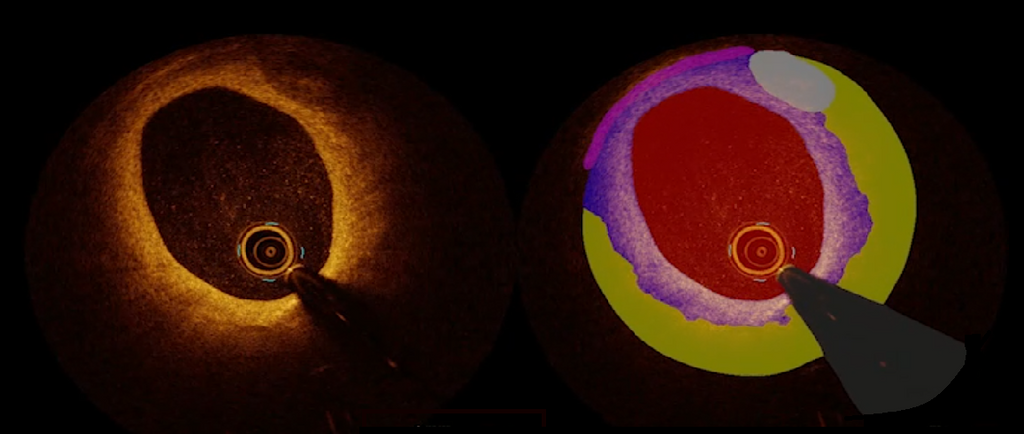

AI for Cardiology

Towards robust and trustworthy AI-systems for real-time analysis of optical coherence tomography (OCT) images at the cardiac catheterization lab.

Read more →